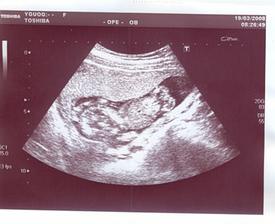

pátek 13/6 - fetální ultrazvuk (v BN nám špatně diagnostikovali rozštěp rtu a patra) u Apolináře, týden z toho nespíme..., výsledek je i navzdory datu dobrý, rozštěp se nekoná!!!, miminko váží 1017g,